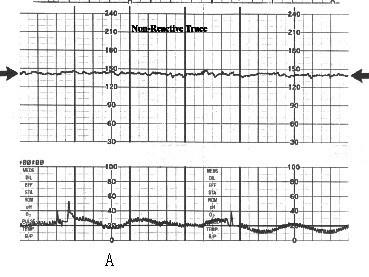

问题 如图A、B、C、D描记的胎心率种类正确的一项 ( )

选项 A、正常胎心率,NST反应型,晚期减速,早期减速 B、基线静止型,NST反应型,变异减速,晚期减速 C、基线静止型,NST反应型,晚期减速,早期减速 D、心动过速,NST无反应型,晚期减速,早期减速 E、正常胎心率,NST反应型,变异减速,早期减速

答案 C